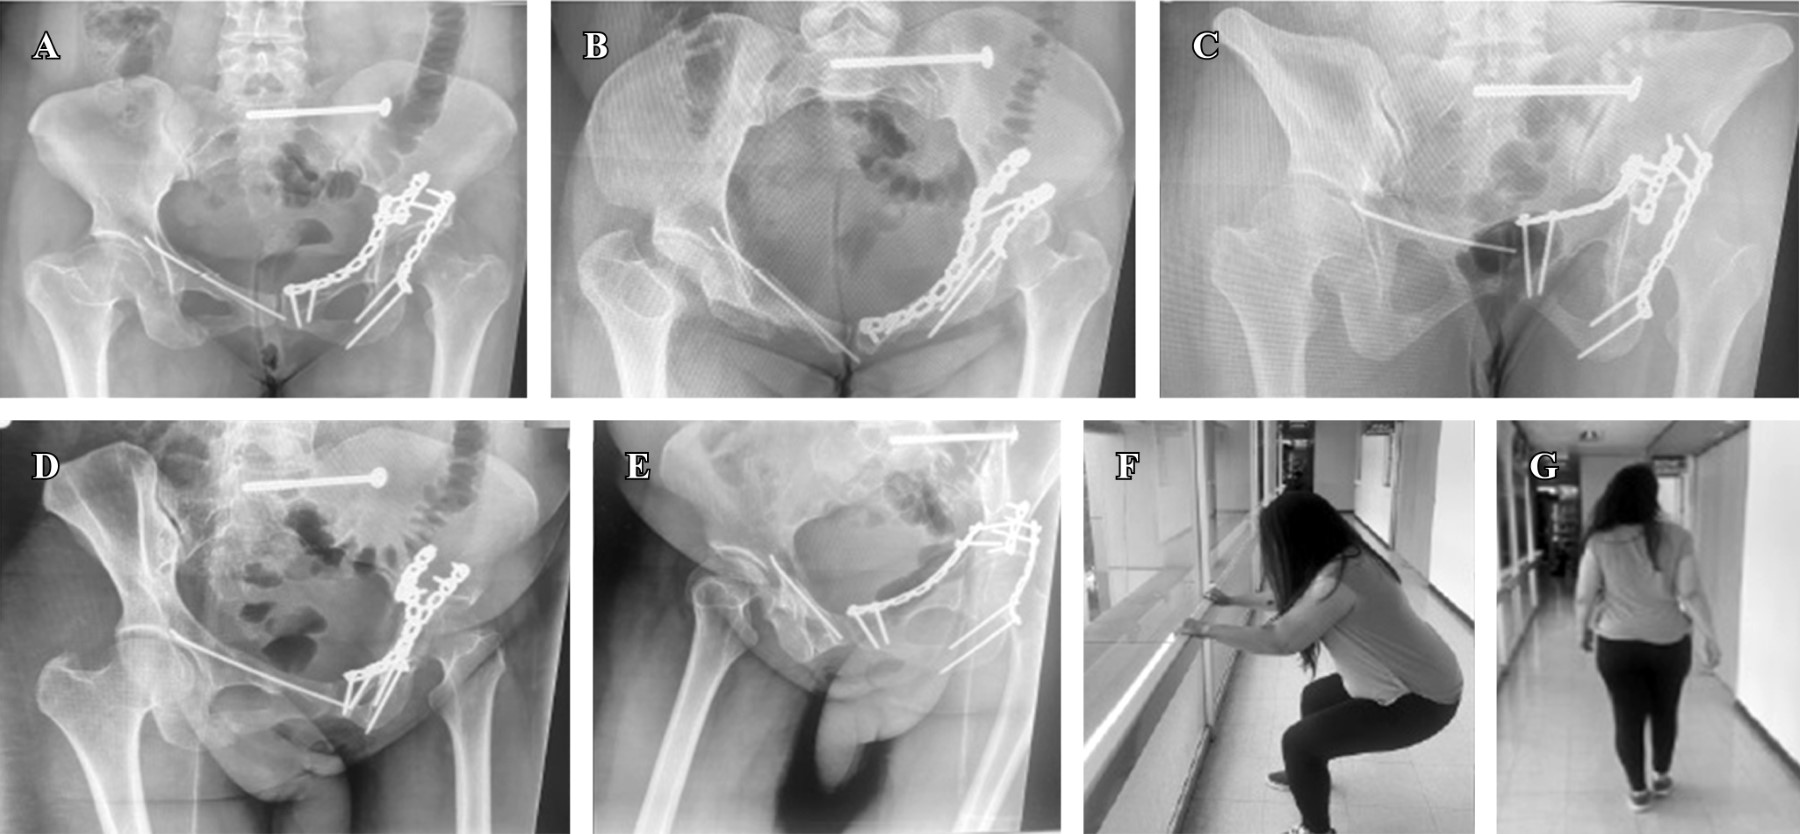

Figura 2